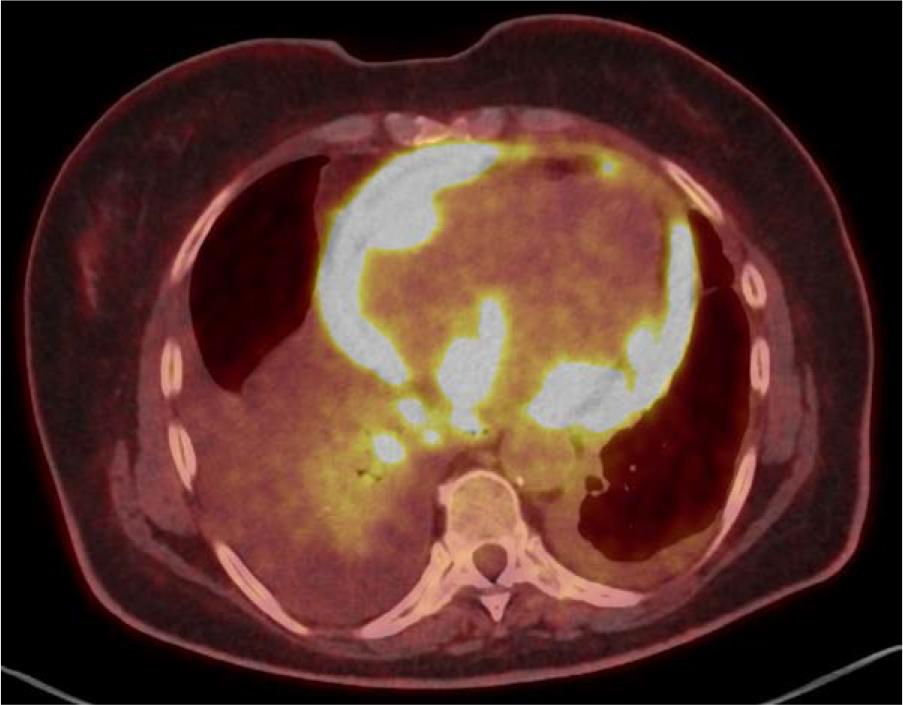

A disseminated proliferative process was identified. Polycyclic adrenal masses were observed — the right measuring 106x61 mm, infiltrating the right kidney and liver, and the left measuring 72x62 mm, infiltrating the left diaphragmatic crus and, marginally, the upper pole of the left kidney. Both lesions were characterized by increased radiotracer uptake, with a standardized uptake value maximum (SUVmax) of approximately 40. Such a high radiotracer uptake strongly suggests a malignant nature of the lesions [14, 15].

[18F]FDG PET/CT, axial plane – the image shows increased radiotracer uptake in the bilateral polycyclic adrenal masses, infiltrating the liver and the left diaphragmatic crus. Focal increased uptake is also visible in the spleen, peritoneum, back muscles, and paraaortic and hepatic hilar lymph nodes.

Additionally, proliferative foci were visualized in the liver, spleen, kidneys, bones, peritoneum, upper abdominal and thoracic lymph nodes, and bilaterally in the pleura. Also, metabolically active nodules in the thyroid gland were observed. Intestinal involvement was inconclusive, with thickening of the cecal wall and a single focus in the sigmoid colon. Given the advanced extent of metastatic disease, it was not possible to identify the primary site. The overall imaging pattern raised suspicion for a lymphoproliferative process and warranted its inclusion in the differential diagnosis.